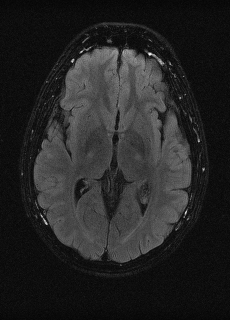

As we observe from the right image in Fig. 2, our BRM, both from MIMO and SISO settings, predicts the performance of dedicated models with a high correlation. We further choose the best three , and perform the last stage of fine-tuning accordingly to (6). A visual evaluation on real data is shown in Fig. 3. For simulated data, please refer to the Supplemental Material section.

Base on the best performing , we perceive that among , , and FLAIR, the results are best when is sampled the most. We suggest that this makes intuitive sense as images provide the best contrast out of the three sequences, which can compensate for the details lost in other images. The same observation can be made on the simulated data, where both and FLAIR show good contrast. When the time setting is changed to non-uniformity, we can see that our search for the best sampling strategy reflects the change. is sampled more as a result of faster acquisition time, while is still sufficiently sampled.

| Sequence | LR | SISO | MIMO | MIMO tuned | GT |

|---|---|---|---|---|---|

(a) 34.38/0.9371

(a) 34.38/0.9371

|

(b) 42.42/0.9883

(b) 42.42/0.9883

|

(c) 44.60/0.9920

(c) 44.60/0.9920

|

(d) 45.50/0.9940

(d) 45.50/0.9940

|

(e) PSNR/SSIM

(e) PSNR/SSIM

|

|

(f) 29.74/0.8903

(f) 29.74/0.8903

|

(g) 36.25/0.9734

(g) 36.25/0.9734

|

(h) 36.42/0.9752

(h) 36.42/0.9752

|

(i) 37.70/0.9832

(i) 37.70/0.9832

|

(j) PSNR/SSIM

(j) PSNR/SSIM

|

|

(k) 39.89/0.9311

(k) 39.89/0.9311

|

(l) 43.94/0.9864

(l) 43.94/0.9864

|

(m) 44.74/0.9883

(m) 44.74/0.9883

|

(n) 45.49/0.9894

(n) 45.49/0.9894

|

(o) PSNR/SSIM

(o) PSNR/SSIM

|